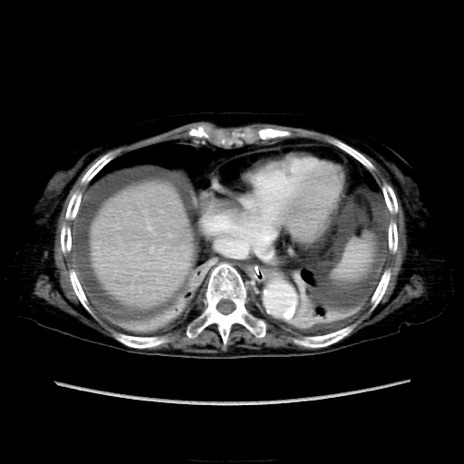

症例40(横断像)

【症例】90歳代女性

【主訴】腹痛・嘔吐

【現病歴】 食欲低下、嘔吐があり昨日他院受診。肺炎と診断され入院となる。入院後より腹部全体に圧痛あり。胃管留置され経過みていたが、症状持続するため、

当院転院となる。

【既往歴】胸椎圧迫骨折、胆石症

【身体所見】腹部:中央に激痛あり、圧痛あり、反跳痛不明

【データ】WBC 17100、CRP 18.82